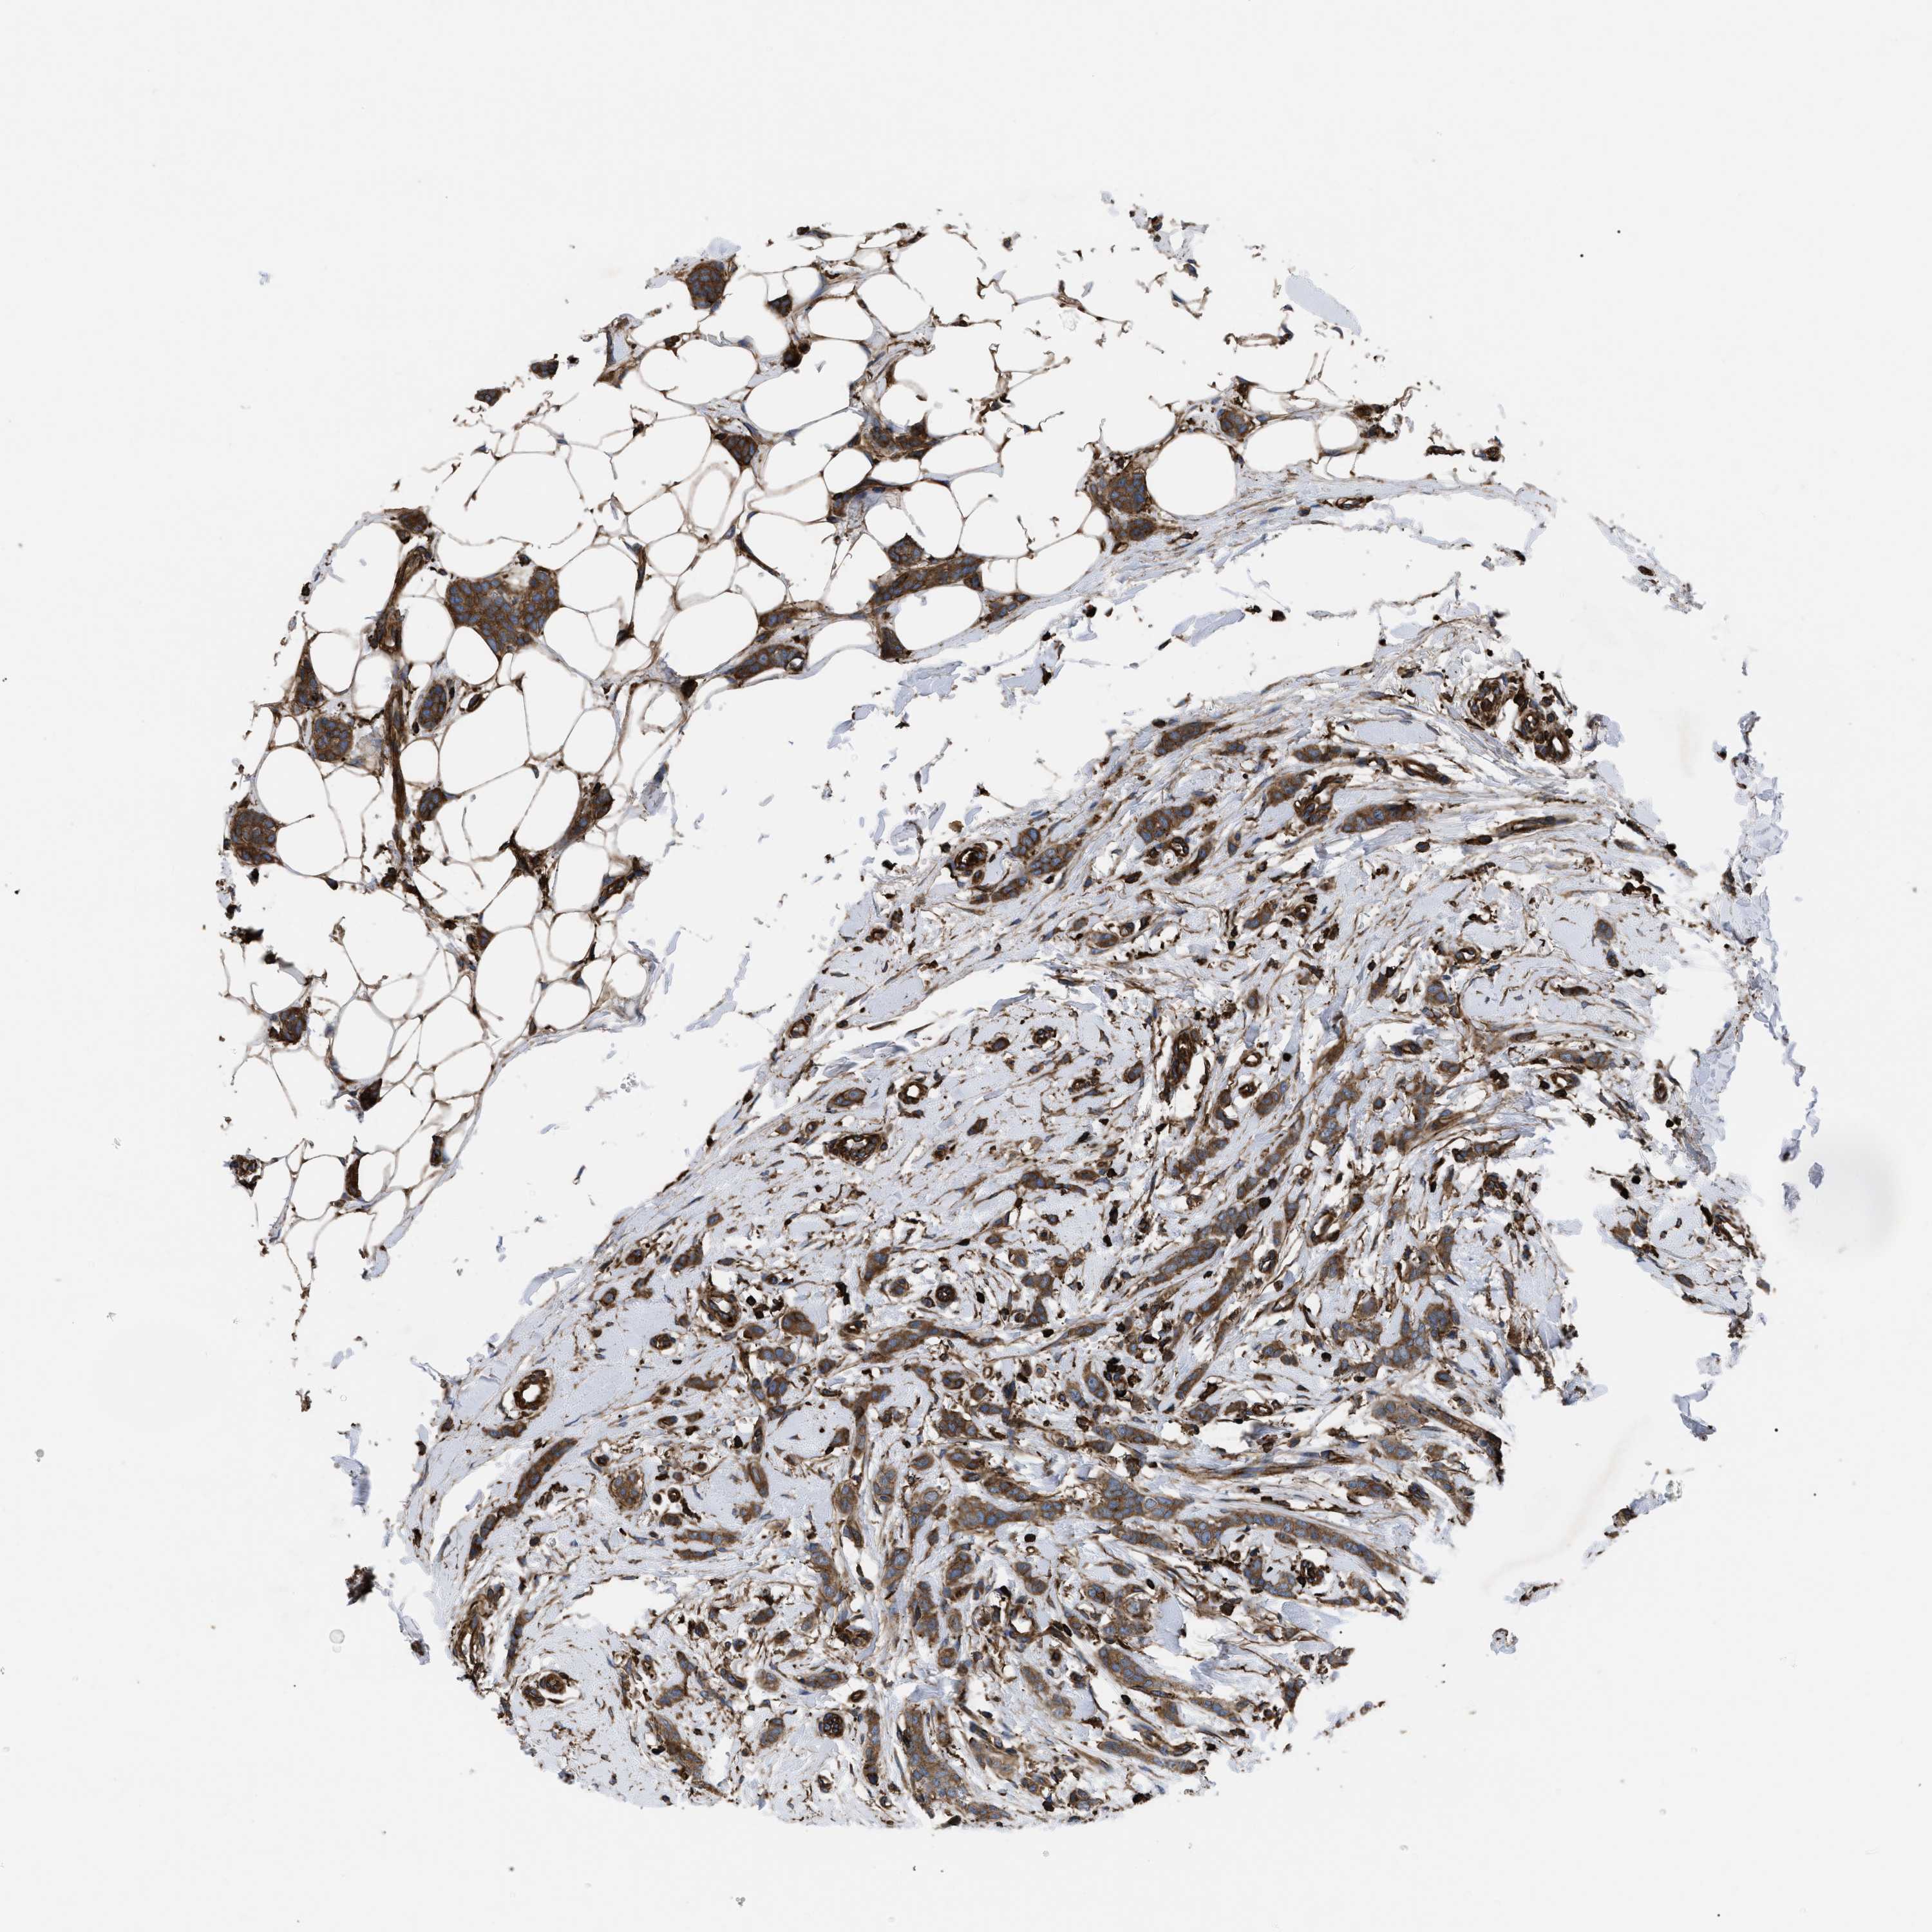

BRCA TCGA BRCA VALIDATION PROTEIN EXPRESSION